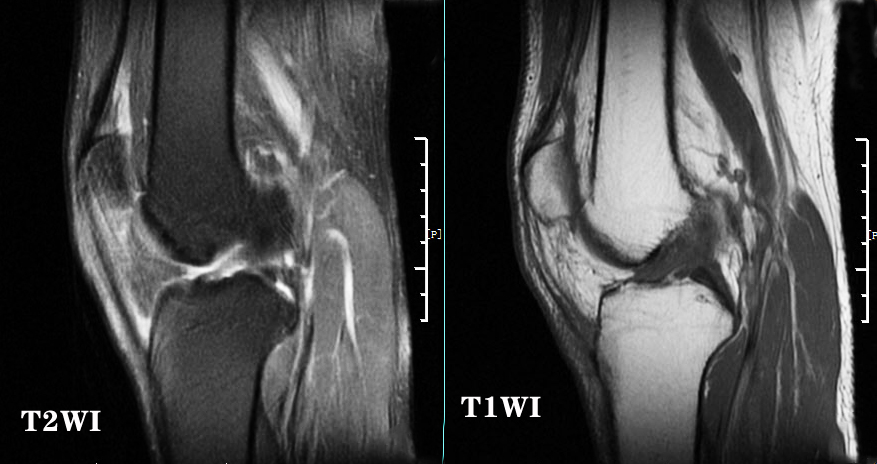

大家需要明白的是T2WI主要看损伤,水肿、血肿等信号,并且在T2WI是高亮信号;T1WI主要看结构,骨骼形态是否正常;看到下图大家就会明白这个意思。